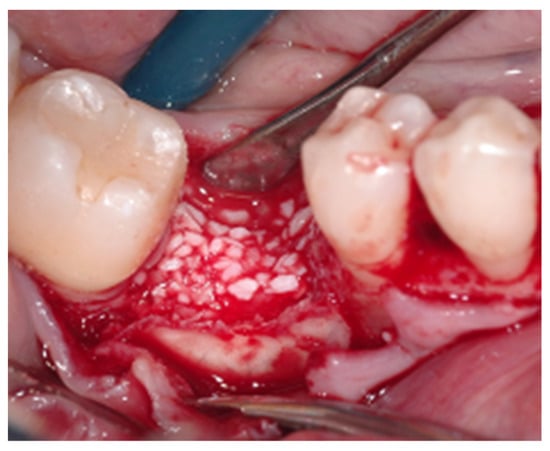

2.2. Surgical Procedure